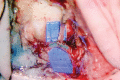

Millions of people worldwide suffer from lymphedema. In developed nations, lymphedema most commonly stems secondarily from oncologic treatment, but may also result from trauma. More recently, lymphedema has been identified in patients after gender-affirmation phalloplasty reconstruction. Regardless of the etiology, the underlying pathophysiology involves blockage of lymphatic flow, resulting in lymph stasis, thus triggering a cascade of inflammation culminating in fibrosis and adipose deposition. Recent technical advances led to the refinement of physiologic and reductive surgeries-including lymphovenous anastomosis and free functional lymphatic transfer, which collectively encompass a variety of flap procedures including lymph node transfer, lymph channel transfer, and lymphatic system transfer. This article provides a summary of our approach in the assessment and management of the lymphedema patient, including detailed intraoperative photography and imaging, in addition to advanced technical considerations in physiologic reconstruction.